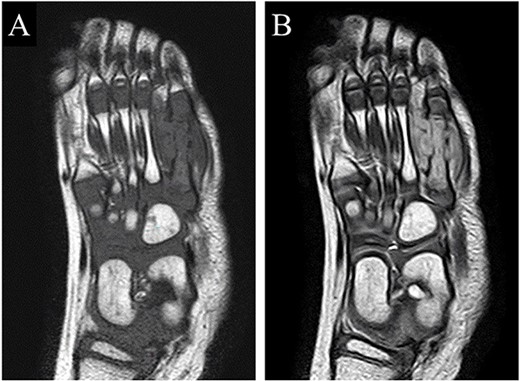

A 21-month-old Japanese female infant presented with a swollen mass on the dorsolateral aspect of the left foot. Her parents noticed the mass and brought the patient to our hospital. The patient had no past medical histories or complications prior to the occurrence. In addition, she received the BCG vaccine at the age of 4 months in Japan. At first visit to our hospital, physical examination revealed the ~3 × 3 cm mass was located on the dorsolateral aspect of the left foot and was hard accompanied by local heat (Fig. 1). Plain radiographs of the left foot showed a lytic lesion without periosteal reaction in the fifth metatarsal bone (Fig. 2). Magnetic resonance imaging (MRI) showed an isointense lesion on T1-weighted images and a hyperintense lesion on T2-weighted images around and within fifth metatarsal (Fig. 3). Gallium scintigraphy revealed intense uptake in the patient’s left foot (Fig. 4). In addition, laboratory examination was within normal. Based on medical history, clinical and imaging findings, we considered the possibility of neoplasia or osteomyelitis and performed an open debridement and biopsy of the lesion to make a diagnosis. The lesion was yellow and consisted of weak, adipose-like tissue that surrounded and continued into the inferior of the fifth metatarsal bone (Fig. 5). The lesion inside and outside the bone was resected as much as possible. Histopathologic examination of the lesion showed granulomatous inflammation including anaplastic giant cells, Langerhans-type giant cells and caseous necrosis (Fig. 6). Based on these results, TB or BCG osteomyelitis was considered as a diagnosis. The tuberculin test was positive, but the QuantiFERON TB test was negative. In addition, samples analyzed using polymerase chain reaction did not identify M. tuberculosis, but did identify the BCG Tokyo-172 strain. Per these findings, the patient was diagnosed with BCG osteomyelitis of the fifth metatarsal and oral treatment with anti-TB medicine including isoniazid (100 mg/day) and rifampicin (150 mg/day) was started. Clinical findings included reduction in swelling of the mass and gradual remodeling of the lytic lesion of the fifth metatarsal on plain radiographs (Fig. 7). However, 10 months after starting the anti-TB treatment, the mass recurred, and MRI revealed a residual high-intensity lesion around and inside the fifth metatarsal on T2-weighted fat-suppressed images (Fig. 8). It was determined that the lesion was difficult to control with anti-TB treatment alone, so an open debridement for the lesion was performed again. Histopathologic examination of the lesion revealed an epithelioid granuloma with necrosis. Therefore, the anti-TB treatment was continued. Six months after the second surgery, clinical and radiographic image findings showed complete improvement (Fig. 9). As a result, anti-TB treatment was ended. At the time of writing this report, 8 years after starting anti-TB treatment, there has been no recurrence.

MRI showed an isointense lesion on T1-weighted images and a hyperintense lesion on T2-weighted images around and within the fifth metatarsal.

MRI revealed that a high-intensity lesion remained around and inside the fifth metatarsal on T2-weighted fat-suppressed images.